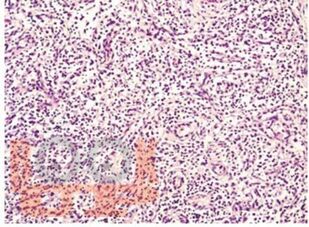

Представлены основные современные сведения по врожденным инфекциям, встречающимся в практике врача педиатра, инфекциониста, неонатолога и оказывающим влияние на беременность, плод и новорожденного ребенка. Особое внимание уделено вопросам эпидемиологии, иммунопатогенеза, клинической картины и лабораторной диагностики, также основным принципам комплексной терапии, профилактики и реабилитации детей с врожденными инфекциями. Обобщены основные сведения по клинической картине, диагностике и лечению рекомендательного характера, определяющих тактику врача с учетом диспансерного наблюдения в декретированные сроки. Авторами сделан акцент на клинические случаи различных нозологических форм врожденной инфекции, с полным клинико-лабораторным спектром обследования и тактикой ведения этих пациентов. Для самоконтроля даны тестовые задания и ситуационные задачи, решение, которых предполагается на практических занятиях.